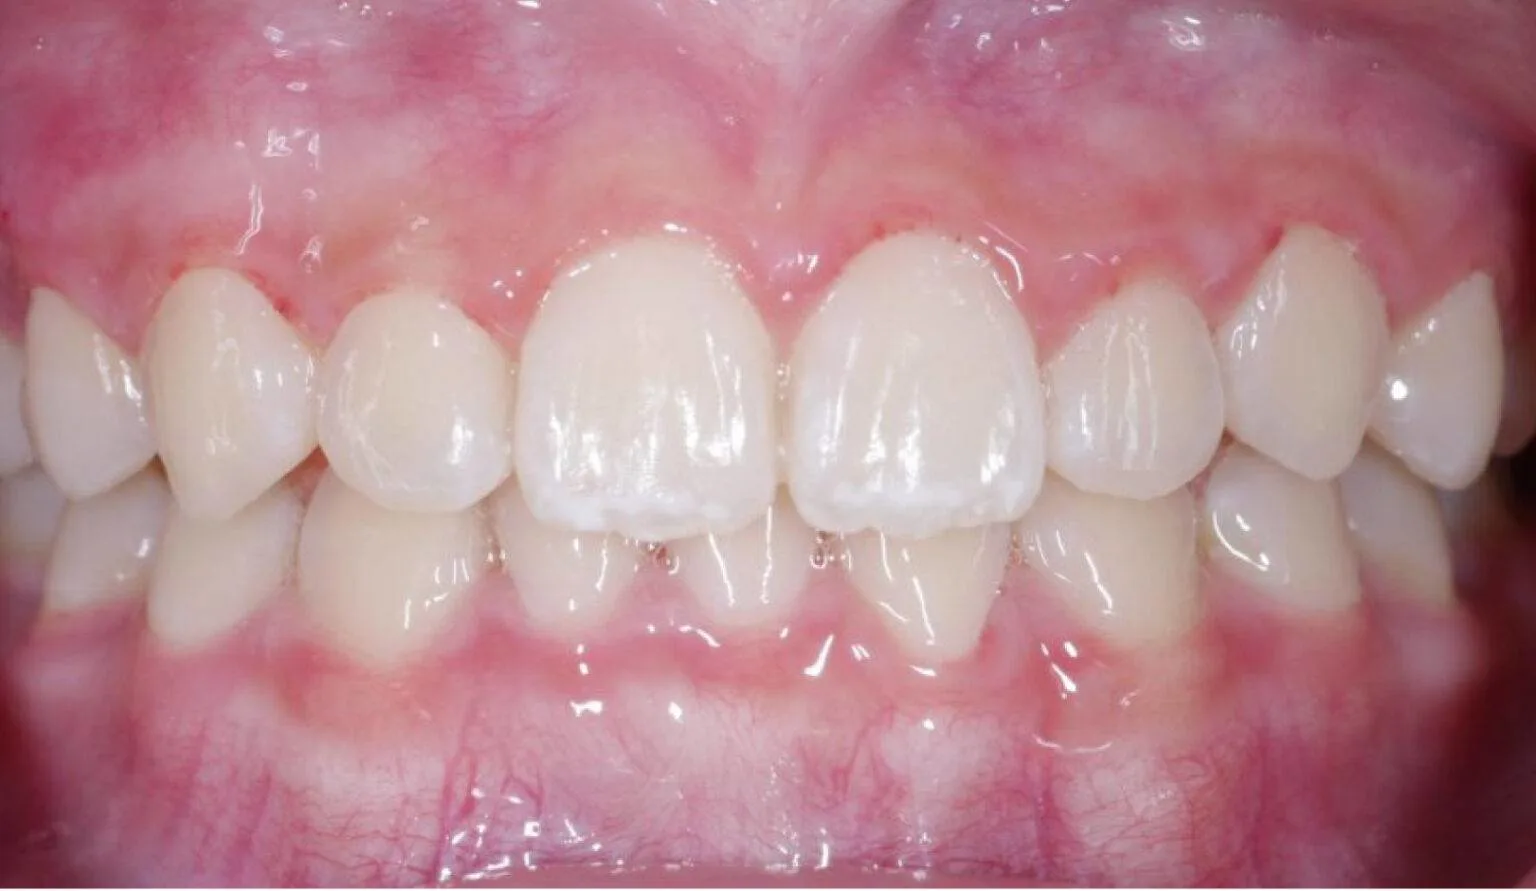

This is where the upper teeth horizontally protrude past the bottom teeth, also called an ‘Overbite’. A common dental complaint we hear that relates to protrusion is ‘my front teeth are sticking out’.

The protrusion of teeth can cause speech problems and make it difficult to consume food, this is due to the fact it can prevent correct biting and chewing.

Protrusion is a dental condition that is usually caused by skeletal issues with the lower jaw, mainly in those who have a growth deficiency. Overbites can cause irreparable soft tissue damage and also contribute to early tooth loss from excessive wear of the teeth. Besides overjets having functional side effects, they can also affect the aesthetics of the smile. Overall, it can look unpleasant to the eye, this can affect a person’s psychological and emotional state.

A dental midline shift is a condition where the centerline of the upper and lower teeth is not aligned properly with the center of the face. In other words, the midline of the upper teeth is not directly above the midline of the lower teeth. This can result in an asymmetrical appearance of the teeth and the face.

A dental midline shift can be caused by a variety of factors, including tooth loss, genetics, facial trauma, or improper dental treatment. Depending on the severity of the condition, treatment options may include orthodontic treatment, dental restoration, or even jaw surgery.

An open bite is a type of malocclusion (misalignment of teeth) where there is a gap or space between the upper and lower front teeth when the back teeth are closed together. This means that the front teeth do not make contact with each other when the mouth is closed, which can cause difficulty in biting and chewing food, speech problems, and jaw pain. Open bites can be caused by a variety of factors such as thumb sucking, tongue thrusting, genetic factors, or abnormal jaw growth.